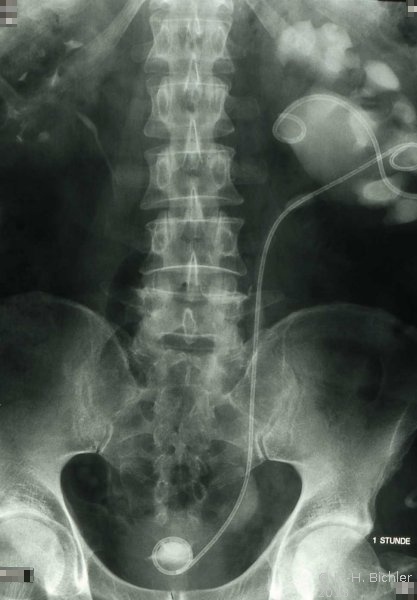

Bei dem Jugendlichen war eine Ureterabgangsstenose nach Anderson-Hynes operiert worden. Wegen postoperativem Aufstau und hochfieberhaftem Harnwegsinfekt war zunächst eine retrograde Sondierung und Einlage einer Ureterschiene erfolgt. Nach Infektbeherrschung Reoperation der Ureterabgangsstenose nach Culp (Abbildung 13).